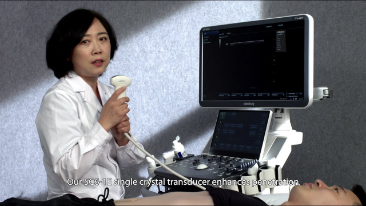

Aparaty ultrasonograficzne z serii Resona, dzi?ki szerokiej gamie za pomoc? wszechstronnych sond do r√≥?nych zastosowaŇĄ i wydajnych narz?dzi do zastosowaŇĄ klinicznych, pomagaj? U?ytkownikom stawia? dok?adniejsz? i efektywniejsz? diagnoz? oraz ocenia? wyniki.

Produkty do obrazowania ogólnego